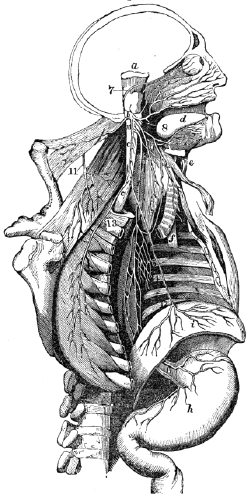

Fig. 8.

Fig. 8. 1, The frontal, or bone of the forehead. 2. The parietal bone. 3, The temporal bone. 4, The zygomatic process of the temporal bone. 5, The malar (cheek) bone. 6, The superior maxillary bone, (upper jaw.) 7, The vomer, that separates the cavities of the nose. 8, The inferior maxillary bone, (lower jaw.) 9. The cavity for the eye.